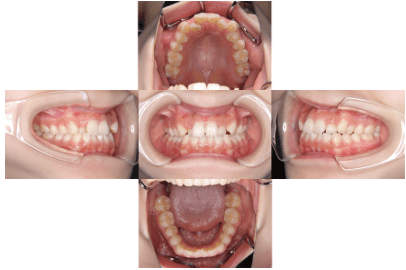

治療前

• 初診時年齢:16歳

• 主訴:叢生

• 診断:叢生を伴う骨格性I級症例、非抜歯

• 治療内容:顎が狭く、上の前歯が後ろに生えてしまい、ガタガタして上手く咬めない状態でした。幅を広くして、歯の角度を調整し、自然な位置に並べたので上手く咬めるようになりました。

• 治療期間:2年

• リスク:ブラックトライアングル(歯と歯の間と歯ぐきの間の三角形の隙間)が強くでる場合がある

• 費用:90万円